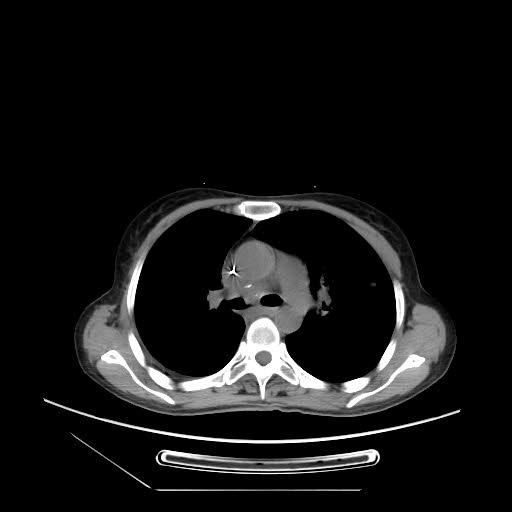

终于,手术成功了,很成功。所有在场的人都舒缓了一口气,胜利总是属于坚持的人,总是属于这些精心准备的人。术后患者咯血止住了,回病房后也没再咯血;病情平稳了。术后两周复查CT显示复发肿块已显著缩小,右侧支气管已复通,患者症状明显改善,安安心心的出院了。

手术后